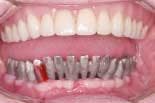

On the day of surgery, the remaining lower teeth are extracted (figure 3) and alveoplasty performed. Branemark Mk III TiU implants were placed in the 37, 36, 34, 44, 46, 47, and 31 sites. Branemark RS TiU implants were placed in the 43 and 33 sites. All implants were torqued to 45 Ncm. Multi-unit abutments were placed on the implants and torqued to 35 Ncm (figure 4). Bioss 1:1 autogenous grafting was done in the anterior region (figure 5) and the sites closed with chromic gut sutures. The maxillary CUD was inserted and the CLD was modified and relined with tissue conditioner.

At the conversion appointment, a measurement of the vertical dimension is recorded. Marks on the nose and chin will serve as reference points (figure 6). The protective caps are removed from the abutments and closed tray impression copings are placed. A full arch polyether impression is made. Prior to removing the impression copings, a centric relation registration is made at the correct vertical dimension utilizing a soft polyvinyl bite registration (figure 7). The soft material is used to allow fit over the impression copings on the stone model. While this will not produce an extremely accurate bite registration, it is sufficient for this purpose. A model of the upper denture is made and a face-bow record taken. Following removal of the impression copings, a cast is produced that represents the implant placement and soft tissue (figure 8). The lower cast is articulated to the upper cast utilizing the bite registration (figure 9).